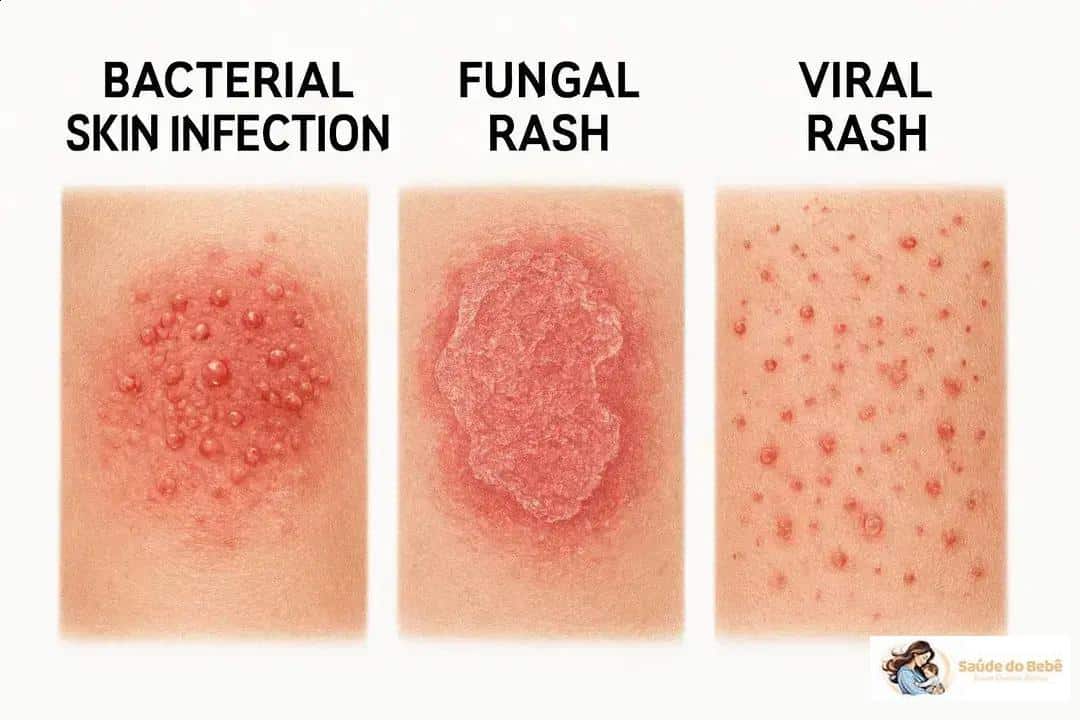

Vários microrganismos podem causar manchas na pele e cada grupo tem sinais próprios. Entender as diferenças ajuda a reconhecer quando tratar ou buscar ajuda médica.

Infecções bacterianas (impetigo, celulite)

Bactérias causam vermelhidão intensa: impetigo aparece com crostas amarelas e exsudato; celulite causa área quente, dolorida e bem delimitada.

Impetigo é comum em crianças e muitas vezes começa como pequenas bolhas que estouram. Celulite pode surgir após um corte ou picada e evoluir rápido, exigindo antibiótico.

Na prática, pus e aumento rápido são sinais que orientam o diagnóstico e o tratamento.

Infecções fúngicas (tinha, candidíase)

Fungos provocam bordas nítidas e coceira: a tinha tem anéis com centro mais claro; candidíase costuma afetar dobras e causar vermelhidão brilhante.

Tinha é comum em pele exposta à umidade, pés ou áreas com fricção. Candidíase aparece após antibióticos ou em pessoas com diabetes.

Um detalhe útil: resposta ao tratamento antifúngico em poucos dias confirma a suspeita clínica.

Infecções virais (herpes, exantemas)

Vírus causam bolhas ou erupções generalizadas: herpes traz bolhas agrupadas e dolorosas; exantemas virais surgem com febre e manchas espalhadas.

Herpes tem episódios recorrentes e dor inicial. Exantemas virais acompanham sintomas sistêmicos como febre e mal-estar.

Se houver febre alta ou muita dor, procure avaliação para evitar complicações e receber tratamento adequado.

- Conheça os Agentes Comuns: Infecções bacterianas (impetigo, celulite), fúngicas (tinha, candidíase) e virais (herpes, exantemas) causam manchas com características distintas.